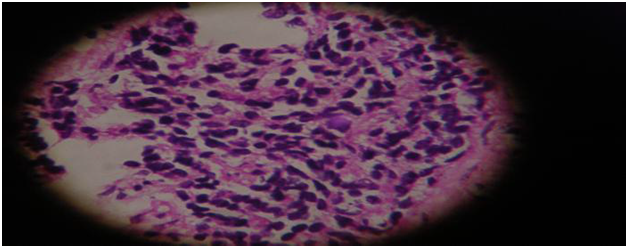

A previously healthy 5year old male child presented with complaints of weakness of both lower limbs. He had fall a week before the presentation of the weakness. His bladder and bowel habits were normal. On Examination Lansky Score 90 - minor restrictions in strenuous physical activity.1 His higher functions were normal, in his motor functions tone was normal, power was 4/5 –right Lower Limb; 3/5- Left lower limb. His deep tendon reflex, plantar and sensory systems were normal. He had scoliosis. On investigations Blood and Urine examinations were normal. Radiograph of the Chest and Ultra sonogram of abdomen were normal. Radiograph of the Dorsal Spine showed scoliosis. Magnetic Resonance Imaging of Brain was normal. Magnetic Resonance Imaging Spine showed Extra Dural mass lesion in the right dorso-lateral aspect of Spinal Cord at D 6-D 8 Vertebral Level causing significant cord compression (Figure 1). He underwent Dorsal Laminectomy with removal of Extradural SOL on 26-04-06. Per-op: Moderately vascular, Greyish fleshy mass, spreading in the extradural space extending from D-6 to D-8 level compressing the spinal cord. Near total excision was done. Pathological findings showed Small round cells with perivascular infiltration and pseudorosettes, suggestive of Malignant Primitive Neuro Ectodermal Tumour of Extra dural Origin (Figure 2). Immmuno Histo Chemistry Studies Done showed CD99 +ve , Vimentin +ve, MIC2 +ve. Post operatively Boy was treated with one cycle of chemo [VAC] Vincristine, Adriamycin, Cyclophospamide. Since there was minimal residue and Malignant histology ,a course of post-op external radiotherapy was planned using Linac using multi leaf collimator, 3D CRT Plan ,the post op tumor bed (with adequate margin ) was treated with Photons-6 MV Dosage: 42Gy in 28 # 150cGy /# over 6weeks using 3 portals. At the end of radiotherapy (Figure 3). Patient was able to walk with Spinal support. Post op and Post RT Post RT 3 more cycles of VAC and 4 cycles of Vincristine, Actinomycin-D, Cyclophospamide alternating with 8 cycles of Ifosfamide and Etoposide were given starting from May 2006 to March 2007 and the patient withstood the treatment without major morbidities. PET scan of the whole body done in Jan 2007 showed Radioisotope: 18F-FDG-370MBq/45min uptake. PET-3D mode and CT Extent of study: Base of skull to upper mid third of thigh, showed no evidence of any active disease anywhere in the body (Figure 4). Patient is now in complete remission and on follow up for 10years (Figure 5).

Figure 2 Slide showing features of PNET Postoperative course.